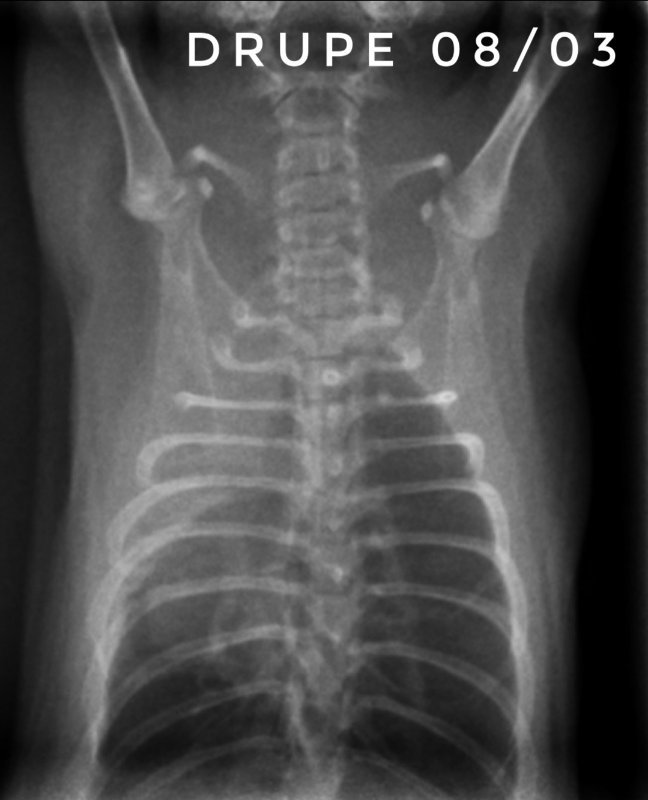

Toujours pour ceux que ça intéresse, les dernières  radios et le suivi du poids (Pyridion a commencé à perdre du poids le 04 mars, traitement changé le 08)

Il nous reste donc 3 malades : Drupe, Caryopse et Pyridion.

Drupe va vraiment mieux, poumons encore touchés mais mieux quand même (mais décidément c'est bien long).